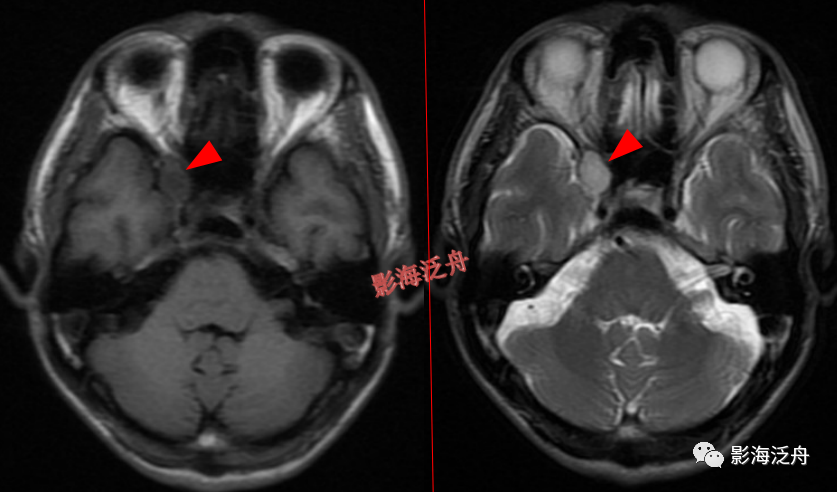

颅骨病变

左侧岩尖部囊性病变(红箭头),患者未术,病理不明。MR对骨质结构显示不佳,因此很多读者会忽略掉颅内骨质病变的观察,很多颅内病变,如三叉神经鞘瘤、鼻咽癌

等都会造成颞骨岩部(红色标注区)骨质破坏,因此,平时应对此处多加留意。黄箭头指听神经及内耳结构。

蝶骨骨纤维异常增殖症(红箭头),病灶内部可见特征性的囊变区(黄箭)。蝶骨的病变在MR上识别起来更为困难,因为蝶骨位于颅底部,此处骨骼、肌肉、脂肪等多种组织成分混杂,导致正常情况下也看起来非常乱。不要着急,慢慢学。